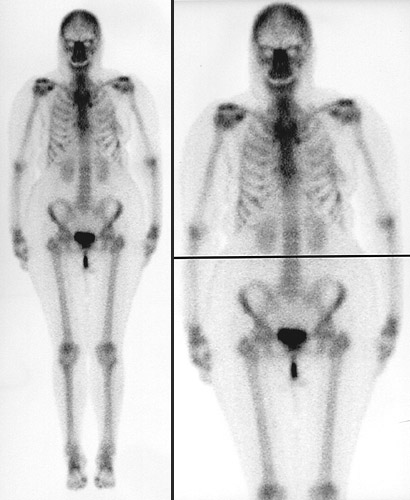

| These composite images in a posterior view above and anteriorly below represent the normal appearance of a bone scan using Tc99. The areas of uptake are even and symmetrical. The only "hot spots" appear in the posterior iliac crests as a consequence of recent bone marrow biopsies. The bladder is also highlighted, along with the catheter, because of excretion of the radioisotope through the kidneys, which are outlined as well. |